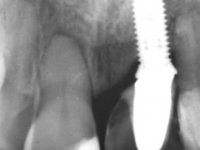

Female patient, 30 years old, non-smoker. The patient appeared in consultation after orthodontic treatment and placement of an implant at tooth site 2.1. Teeth 3.7, 3.6 and 4.7 had root canal therapy and teeth 1.5, 2.5, 2.6 and 4.5 had undergone extensive restorations. Patient had a thin periodontium and showed a satisfactory oral hygiene. After surgical exposure of the implant, it proved to be positioned improperly. Prosthetic rehabilitation of the implant proved impossible by adopting acceptable aesthetic criteria. The patient carried an acrylic temporary crown on a stump screwed as a fallback solution for six years, as she had not accepted the offer to remove the implant. After this time, patient returned to consultation with an abscess in tooth 1.1. After analyzing the situation, it was verified that teeth 1.1 and 2.2 had indicated extraction and the implant should be removed or submerged.

In the initial phase, it was proposed to the patient to perform the surgical implant exposure and after clinical evaluation, make prosthetic decisions. Once the healing screw was placed and the soft tissues were healed, an inadequate position of the implant was found. In view of the dramatic situation, the patient was proposed to remove the implant and put a new one after tissue regeneration. This proposal was rejected by the patient, who suggested temporary rehabilitation of the current implant. A new proposal was then made, to rehabilitate the implant, consisting of a screwed abutment, and on this, the placement of an acrylic crown with coronal and gingival components. After 6 years with the provisional treatment, the patient appeared in consultation with an abscess in tooth 1.1. After clinical and imaging analysis, it was decided to remove teeth 1.1 and 2.2, submerge the implant, place two implants at the site of 1.1 and 2.2 and perform adequate tissue regeneration. Temporization would be done with a provisional 3-element bridge, adhered with a net to the neighboring teeth. After osseointegration, definitive rehabilitation would be done with a 3-element bridge, including zirconia infrastructure and ceramic cover.

The surgical implant exposure and the healing screw placement proved to be a negative surprise regarding its position. Since the proposed removal of the implant was refused, we advanced to its provisional rehabilitation. An open tray impression technique was done, and a screwed abutment with a coronal and gingival component and an acrylic crown were made in the laboratory, using these two components. The provisional crown was placed in the mouth until a final decision was made. Six years passed before the patient returned to the clinic with an abscess on tooth 1.1. The choice to remove teeth 1.1 and 2.2 was made, to create a provisional 3-element bridge with a net to be adhered to the adjacent teeth. Surgery was planned and performed, placing the two implants at the site of 1.1 and 2.2, and the implant at the 2.1 site was cut with the objective of submerging it, while adequate tissue regeneration was performed (Surgical Work performed By Dr. Manuel Neves). During osseointegration, the patient used the fixed provisional bridge. A first impression was made for confection of a zirconia screwed provisional bridge, which worked the soft tissues for twelve weeks. The definitive impression was made with the individualisation of custom impression copings. Final rehabilitation was done with ceramized abutments, and also a bridge with zirconia infrastructure and ceramic cover. Due to the inclination of the implant placed at the site of tooth 1.1, the bridge required cemented fixation.